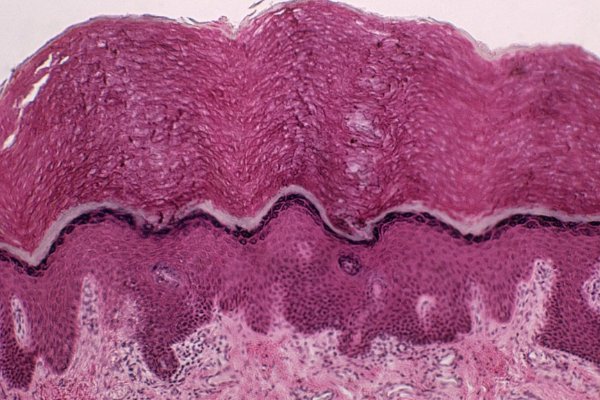

再说,以前在治疗癌症患者的时候,医生不知道有这个新器官,直接进行放射性治疗。虽然放射性治疗能杀死癌细胞,但是一样能杀死正常细胞,比如唾液腺。简单说就是只要医生避开这个新器官,那么癌症病人出现并发症的情况会下降,不会跟之前一样说话、吃饭、吞口水都有问题,新器官发现对于癌症患者来说,妥妥的福音。